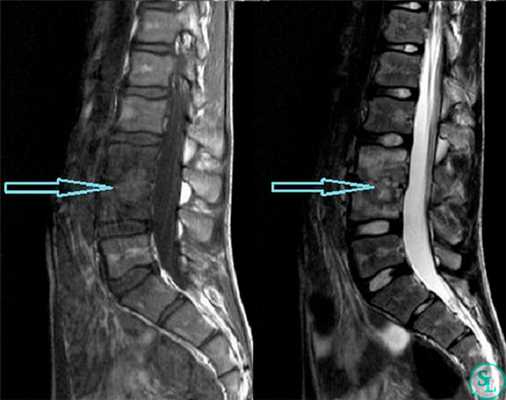

- МРТ позвоночника. Определяется снижение интенсивности сигнала на Т1-взвешенных снимках и его повышение на Т2-взвешенных изображениях, деформация межпозвоночных дисков, структурные изменения тел позвонков. Чувствительность магнитно-резонансной томографии достигает 96%, точность – 94%, поэтому ее считают «золотым стандартом» диагностики.

В диагностике заболеваний позвоночника большей популярностью пользуется магнитно-резонансная томография (или точнее «ядерно-магнитно-резонансная»), более безопасная и чувствительная, чем жесткое рентгеновское излучение. На снимках костные структуры получаются черными, но мягкие ткани, наполненные водой, передают все оттенки серого и белого цветов. Это позволяет обнаруживать мельчайшие объекты (узелковые образования, инфильтрации) и отслеживать динамику развития абсцесса.

- МРТ таза. Исследование показывает активный воспалительный процесс в области крестцово-подвздошных сочленений, которое характерно для первой стадии сакроилеита. Активность воспаления оценивают по силе гиперинтенсивного сигнала в Т1 режиме, что соответствует отеку костного мозга.